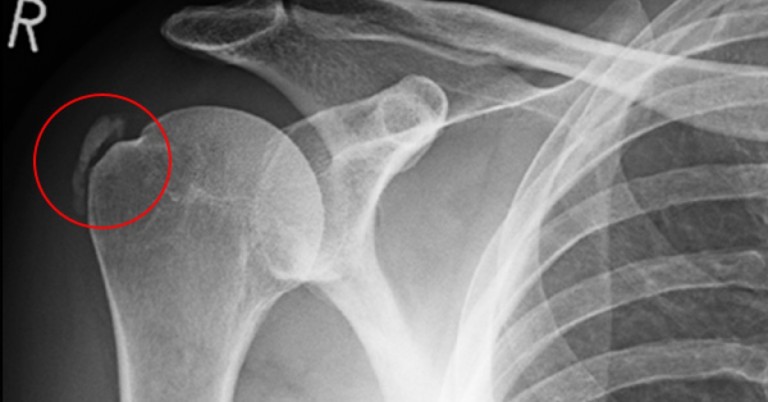

Tout sur la calcification de l’Epaule

Tout sur la calcification de l’Epaule Les calcifications sont responsables de 15% des épaules douloureuses, et sont alors l’objet de multiples questions de la part nos patients … d’où l’idée de cet article. Vous saurez tout (du moins l’essentiel) sur ce trouble en général assez peu connue des patients mais aussi des soignants. La calcification de […]